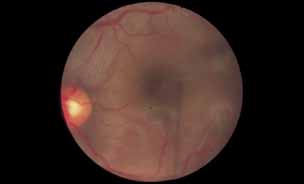

Fig. 4 Luetic neuroretinitis. Color photograph showing placoid opacity at the level of the retinal pigment epithelium.

Fig. 5 Luetic neuroretinitis. A late frame of the angiogram in Figure 4 shows extensive staining of the entire area corresponding to leakage into the outer retina and staining of the pigment epithelium. The patient was successfully treated with intravenous penicillin therapy and subsequently developed diffuse “leopard spot” changes in the pigment epithelium characteristic of resolved luetic neuroretinitis.